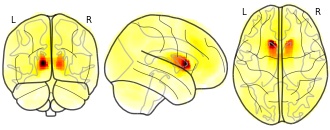

pnajdz's temporary collection: L anterior Caudate -12_16_8

EmailClick to copy linkLink copied Cite(2019). pnajdz's temporary collection: L anterior Caudate -12_16_8 [Dataset]. http://identifiers.org/neurovault.image:295227Unique identifierhttps://identifiers.org/neurovault.image:295227Dataset updatedOct 3, 2019License

Cite(2019). pnajdz's temporary collection: L anterior Caudate -12_16_8 [Dataset]. http://identifiers.org/neurovault.image:295227Unique identifierhttps://identifiers.org/neurovault.image:295227Dataset updatedOct 3, 2019LicenseCC0 1.0 Universal Public Domain Dedicationhttps://creativecommons.org/publicdomain/zero/1.0/

License information was derived automaticallyDescriptionCollection description

None

Subject species

homo sapiens

Modality

fMRI-BOLD

Cognitive paradigm (task)

rest eyes open

Map type

Z